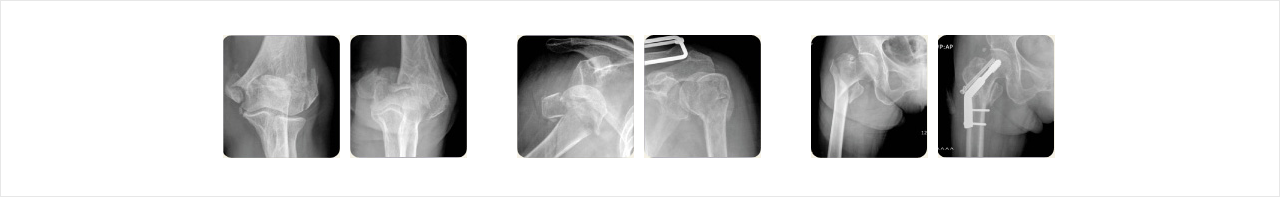

골다공증에 의한 골절

골다공증은 발생되면 이전 상태로 회복되지 않습니다.

하지만 규칙적인 운동과 충분한 영양 섭취등 기본적인 예방법 외에 골다공증이 더 이상 진행하지 않도록 하는 여성호르몬이나 약해진 뼈의 골량을 증가시키는 약제 등을 통해 골절의 위험성을 감소시킬 수 있습니다.